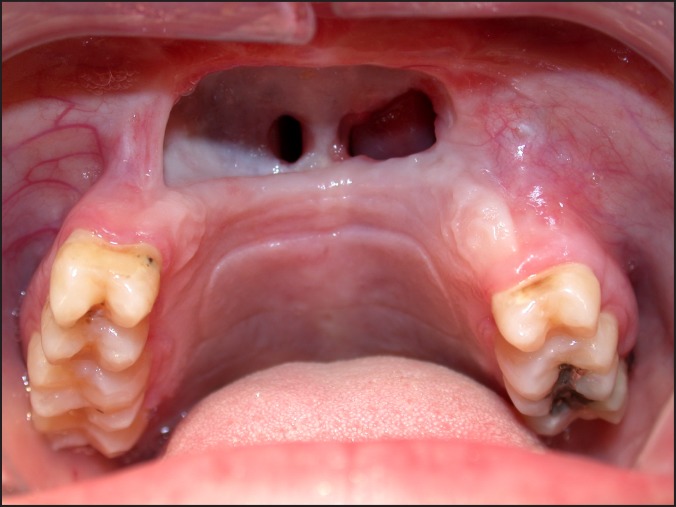

Results: In total 35 literature sources were obtained and reviewed. The topics covered in the second part of this review series include hardware failure, scars and fistula formation; complications associated with choice of reconstruction, donor site morbidity as well as functional and aesthetic issues.

Conclusions: Cancer resection should be planned around two very important concepts. First and foremost is the eradication of disease. This should be the ultimate goal of the ablative team and all potential complications that may be the result of appropriately executed oncologic resection should be discussed in details with the patient. Adequate reconstruction of the defects with restoration of form and function is the second, but not of less importance, goal for the successful care of the head and neck cancer patient.